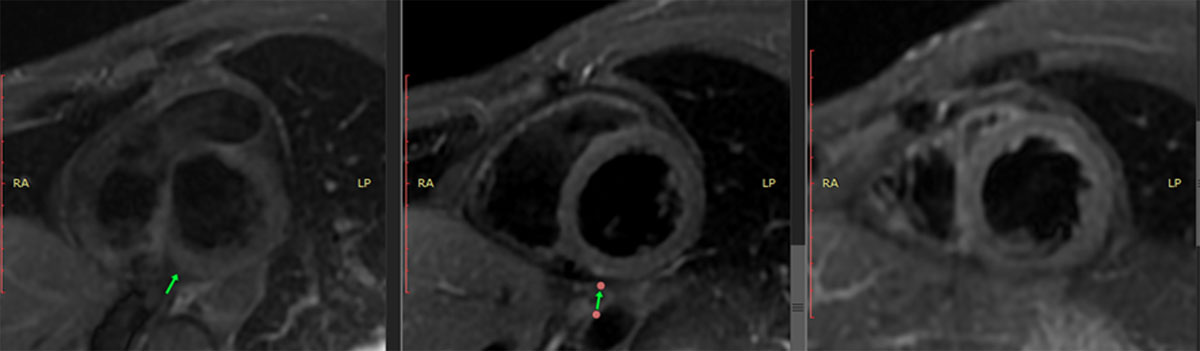

Figure 4

Cardiac MRI with triple IR sequencing showing hyperintense signal, compatible with myocardial edema.